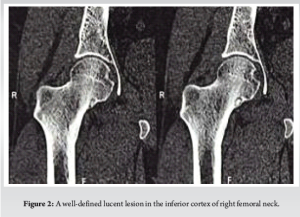

Case Report: We present a case of a 21-year-old male who initially presented with persistent right hip pain. Initial magnetic resonance imaging revealed marrow edema in the right femoral neck with associated joint effusion, leading to a preliminary diagnosis of stress fracture and subsequent misdiagnosis of AVN. The patient’s symptoms persisted despite conservative management. After 6 months of continued symptoms, computed tomography (CT) imaging revealed a characteristic lucent lesion in the inferior cortex of the right femoral neck, confirming the diagnosis of osteoid osteoma. The patient underwent successful radiofrequency ablation (RFA) performed in three cycles.

A 21-year-old male presented with persistent right hip pain that significantly impacted his daily activities. The patient’s initial symptoms began in May 2024, prompting medical evaluation including magnetic resonance imaging (MRI) of the hip. The initial MRI revealed marrow edema in the right femoral neck with associated hip joint effusion and periarticular soft tissue changes. While no definitive signs of AVN were observed, the presence of a stress fracture in the right femoral neck led to the administration of zoledronic acid. Concurrent lumbar spine imaging revealed multiple levels of degenerative changes, including a mild foraminal disc bulge at L3-L4, significant changes at L4-L5 with bilateral nerve compression, and disc protrusion at L5-S1. These findings complicated the clinical picture, potentially contributing to the diagnostic challenge. The patient’s condition progressed, and by July 2024, he experienced worsening hip pain with reduced range of motion. Based on the clinical presentation and previous imaging findings, he was diagnosed with AVN and a femoral stress fracture, leading to a conservative treatment approach with analgesics for 10 days. In October 2024, the presence of a vascular valley was noted, and the patient was advised on lifestyle modifications and dietary changes. Due to persistent symptoms, a repeat MRI was performed in November 2024, which showed mild-to-moderate right hip joint effusion with synovial thickening and subtle marrow edema in the right femoral head, neck, and acetabular roof. Notably, this study did not demonstrate definitive AVN changes, prompting further diagnostic investigation. By December 2024, the patient reported progressive pain radiating from the hip to the right thigh. A computed tomography (CT) scan revealed a critical finding: A characteristic lucent lesion in the inferior cortex of the right femoral neck, consistent with an osteoid osteoma. This discovery led to a definitive change in diagnosis and treatment approach. The patient underwent radiofrequency ablation (RFA) of the osteoid osteoma, performed in three cycles. This case highlights the diagnostic challenges in differentiating between osteoid osteoma and AVN, particularly in young patients presenting with hip pain. The evolution of imaging findings and the importance of maintaining a broad differential diagnosis were crucial in reaching the correct diagnosis. The case also demonstrates the value of advanced imaging techniques, particularly CT scanning, in identifying subtle bone lesions that may be missed on initial MRI studies (Fig. 1-3).